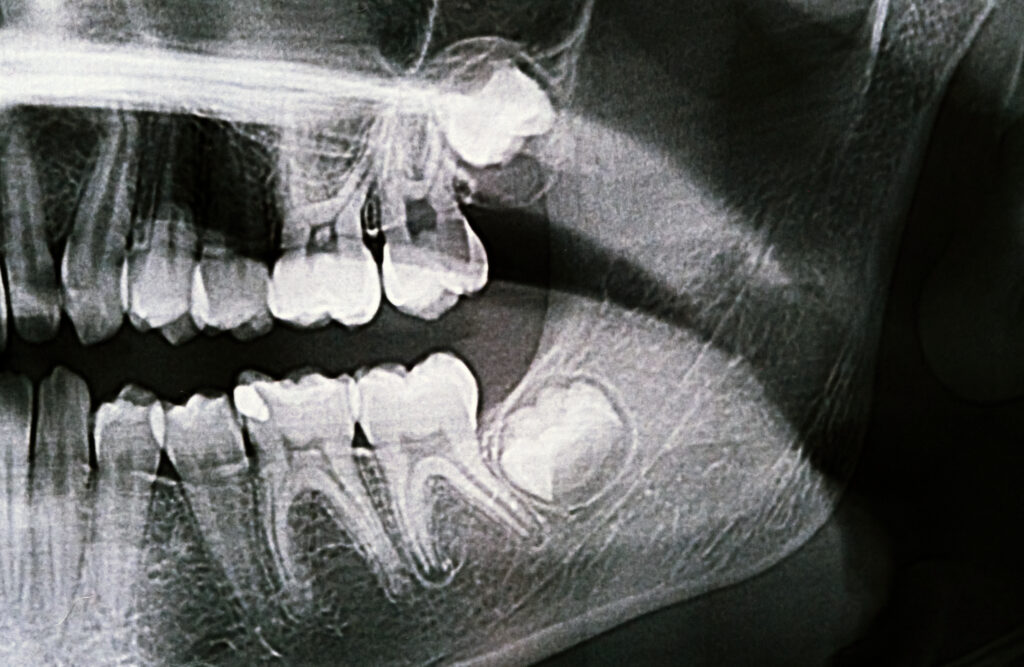

A beavatkozás előtt panorámaröntgent (indokolt esetben CT felvételt) készítünk, hogy pontos képet kapjunk a fog helyzetéről.

Bölcsességfog akadályozott előtörése